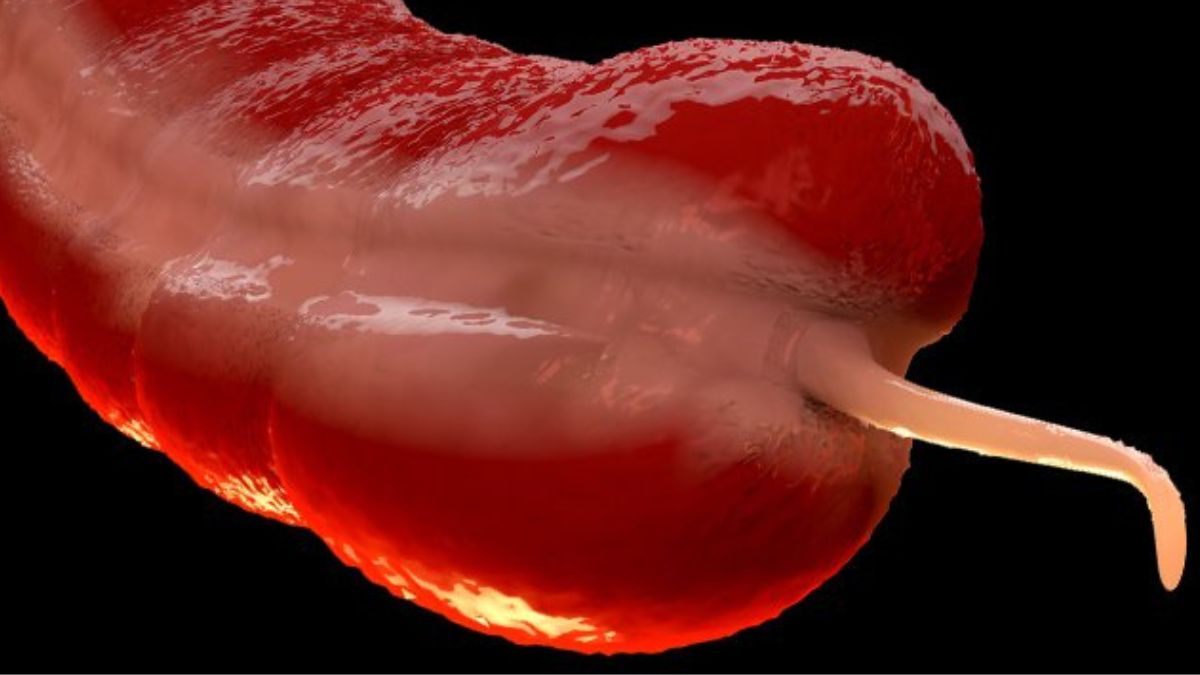

Recent research in the US reveals that Gen X-ers and Millennials are three to four times more likely than older generations to be diagnosed with cancer of the appendix, the finger-sized organ hanging off our digestive tract that few think about unless something goes awry.

For a long time, the appendix was dismissed as vestigial, a leftover organ with no real function. But recent evidence suggests it may not be so useless after all.

Inflammation of the appendix, or appendicitis, is the most common complication associated with the organ, and, on very rare occasions, cancer is found when the appendix is removed.